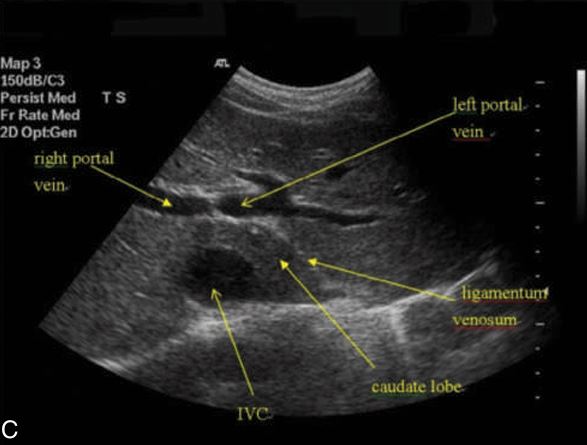

ligamentum venosum

SAG - showing ivc with caudate lobe

TRANS - ligamentum venosum